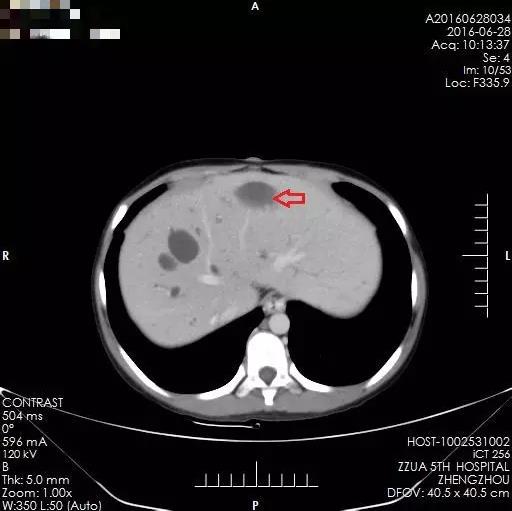

术后2年,箭头所示为肝肿瘤切除后

术后2年,箭头所示为多发肝内胆管囊样扩张

之后的两年里,小夏定期来院复查,肝脏内无肿瘤复发表现,病情平稳。然而,虽然解决了肝脏内肿瘤问题,但小夏的肝脏存在先天性胆管扩张、肝硬化及门静脉高压,食管下段、胃底及腹腔内有明显的静脉曲张,门静脉高压仍然缓慢进展,两年后因上消化道出血再次来到郑州大学五附院。完善相关检查,肝内未见肿瘤复发迹象,但门静脉高压症状明显,为预防再次消化道出血,缓解门静脉高压,经全面术前评估,小夏于2016年8月接受了全麻下行食管下段、胃底贲门周围血管离断术、脾动脉结扎、脾肺分流术。手术顺利完成,术后恢复良好,无任何并发症,术后定期复查,肝内未见肿瘤复发表现,门静脉高压有所缓解,病情平稳,小夏未再出现呕血。